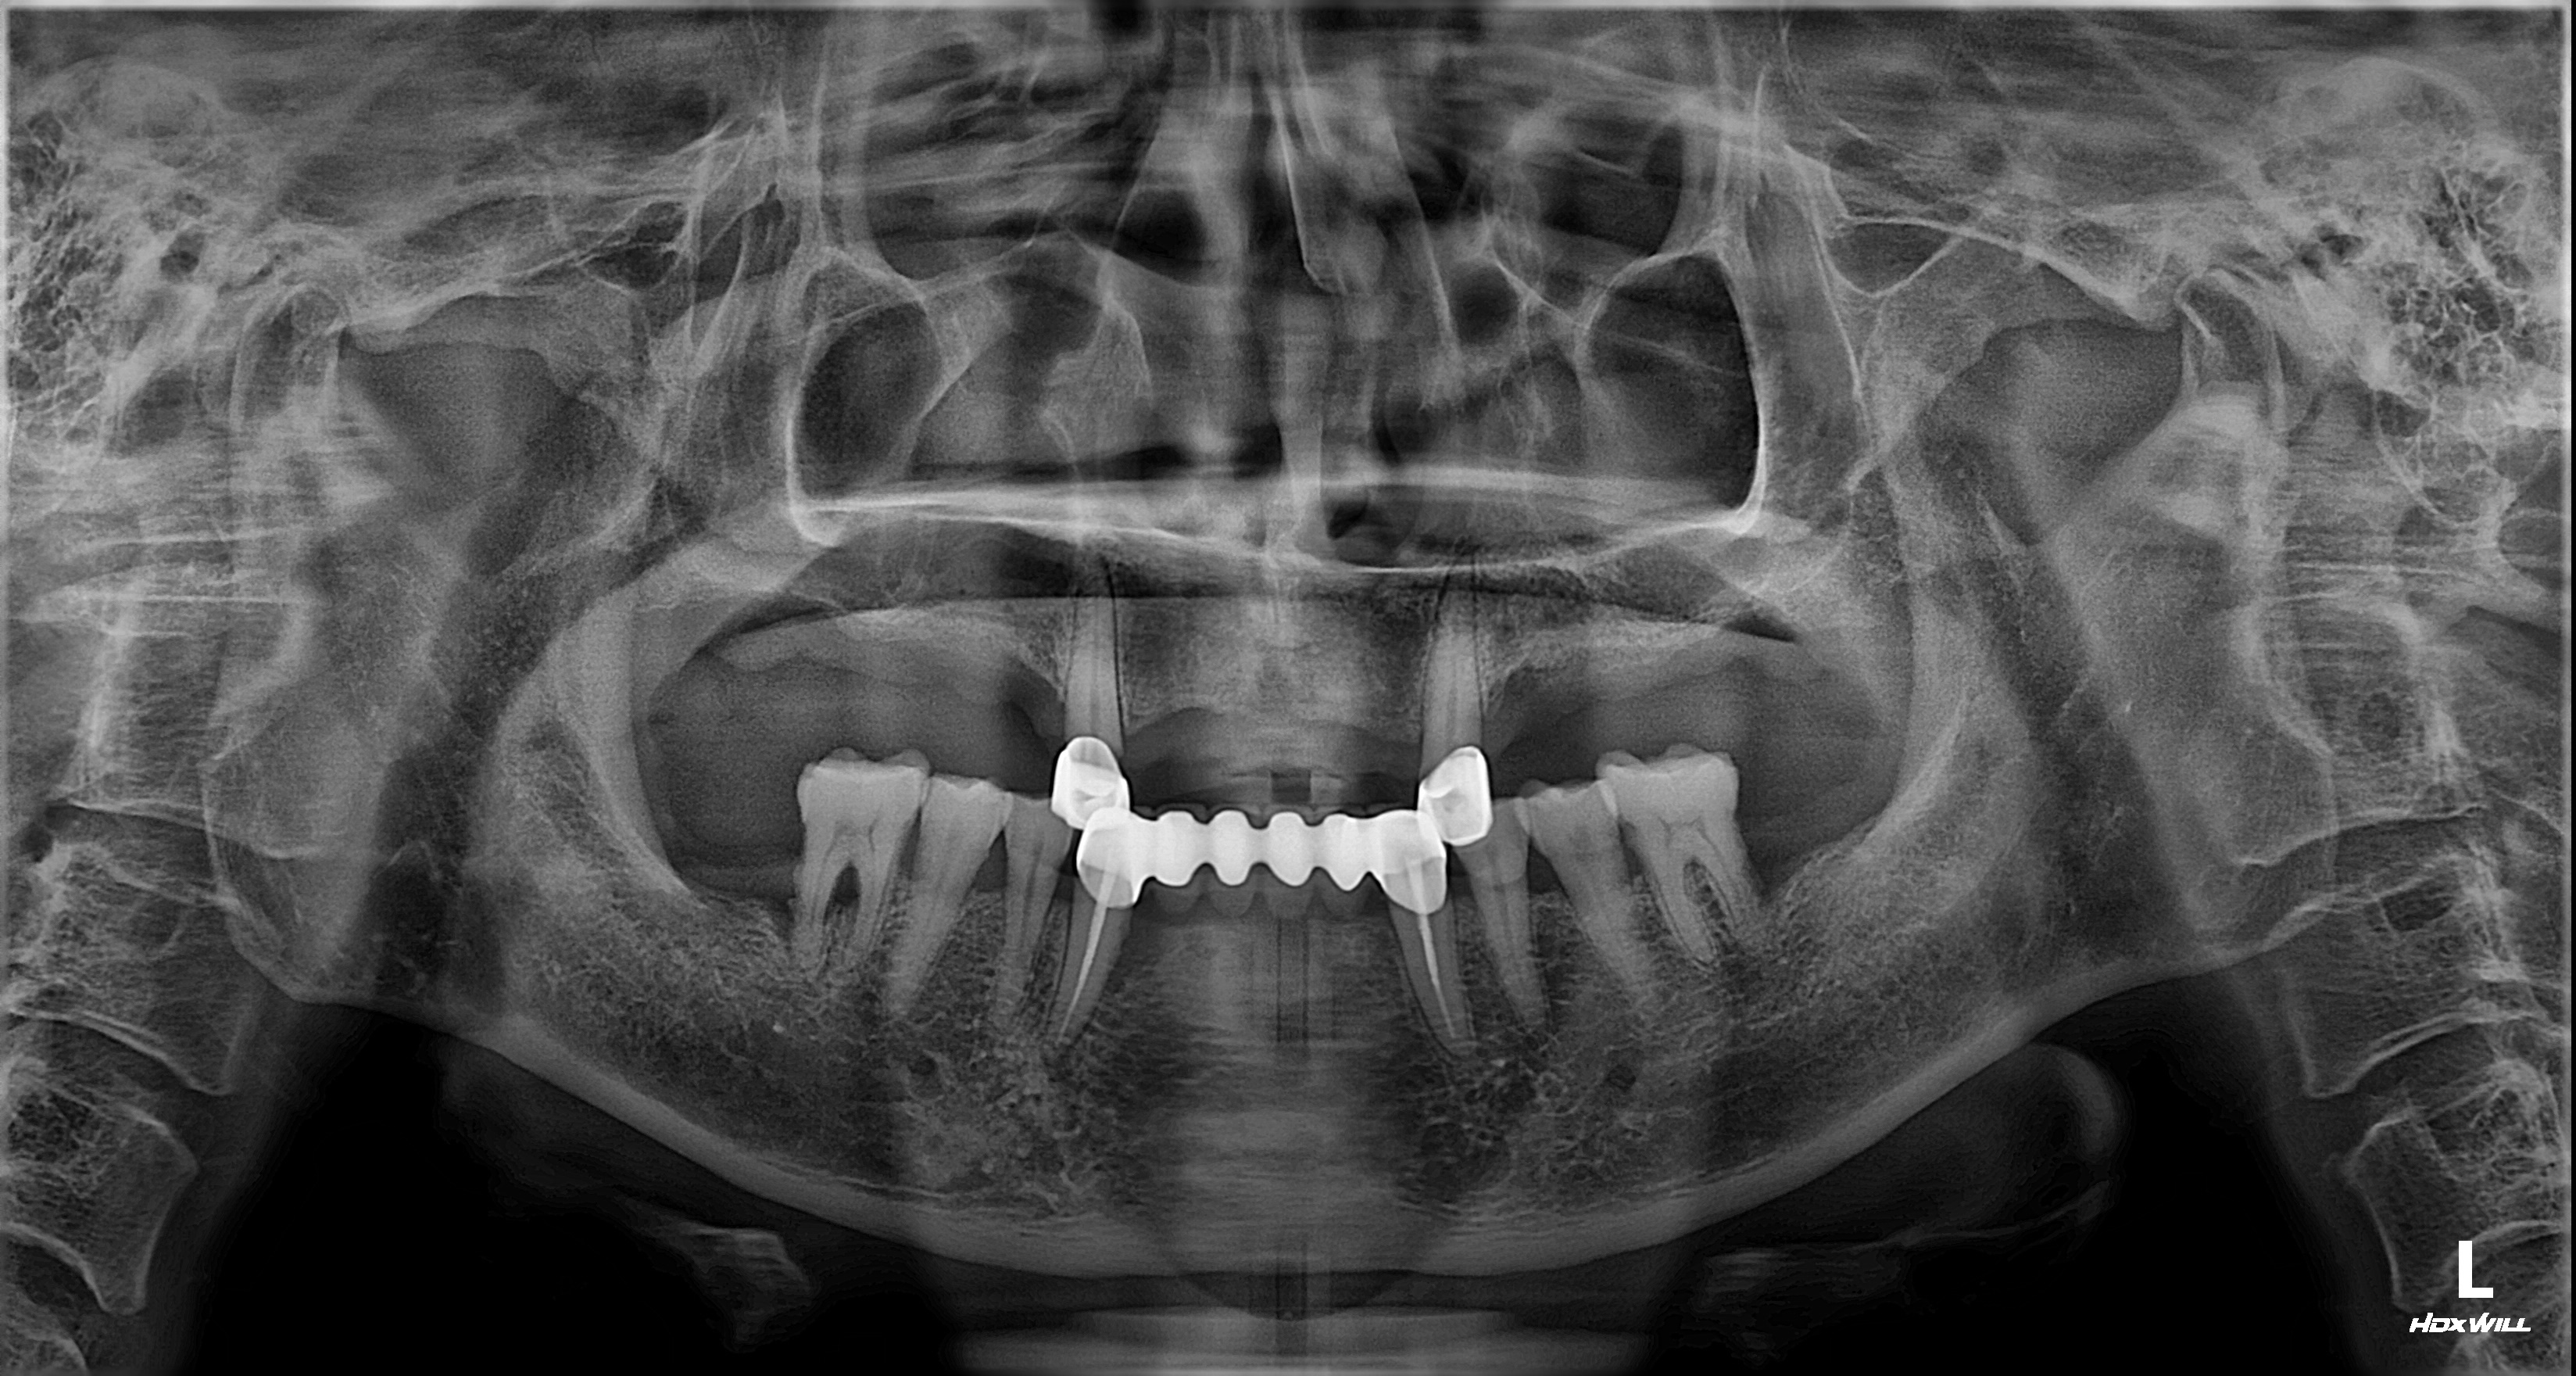

촬영일시: 2025.08.31.

촬영일시: 2026.03.10. [ 치료기간: 2025년 09월 20일 ~2026년 02월 21일 ] ※ 365서울앞선치과의원의 모든 컬럼은 각 진료과 의료진이 직접 작성합니다. 365서울앞선치과의원 임상 케이스 게시물은 환자분께 의학적으로 정확하고 상세한 정보를 드리기 위해 각 진료과 의료진이 직접 작성하며, 모든 증례 사진은 본원 의료진이 직접 시술한 증례를 촬영한 것으로, 의료법 제23조, 제56조에 의거하며 환자분의 동의를 얻어 포스팅에 사용하였습니다. 또한 해당 케이스는 본 환자분의 치료 결과이며, 환자 상태에 따라 치료의 결과는 달라질 수 있습니다. |